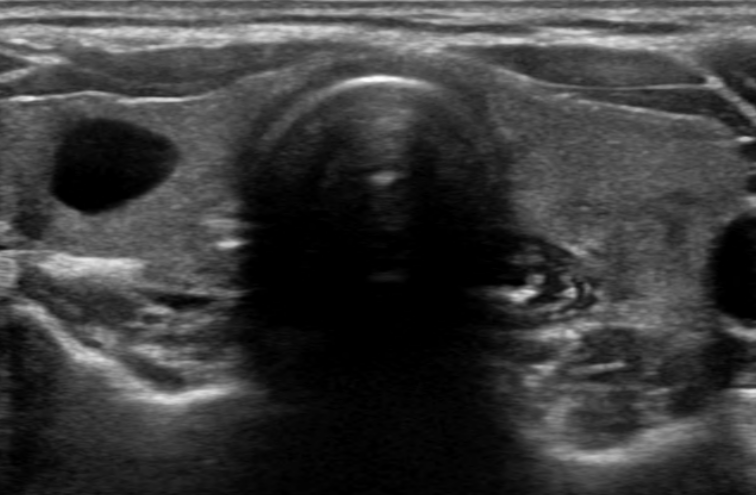

갑상선 낭종의 진단에는 주로 초음파 검사가 사용됩니다. 초음파는 방사선 노출이 없고 안전하기 때문에 널리 활용됩니다.

1) 초음파 검사: 낭종의 위치, 크기, 내부 구조를 파악합니다.

갑상선 안에 물 같은 액체로 채워진 주머니 모양의 구조물이며, 쉽게 말해 갑상선에 있는 물집이라고 생각하면 되겠습니다. 그러나 갑상선 낭종은 때때로 고체 성분을 포함하는 경우도 있는데 이런 경우에는 드물게 암과 관련이 있는 경우도 있기 때문에 관리 및 추적검사가 필요합니다.